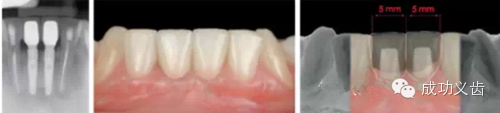

图7.众所周知,相连2颗下前牙的种植修复,考验医师的美学种植控制功力。

图8.相邻2颗下前牙,凸显美学种植控制功力,术后及模式图。在2015年4月3-5日的课程中,Dr.Gamborena将和大家分享他处理这类病例的技巧。绝对干货哦!